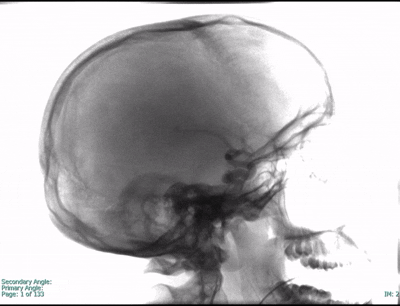

Cerebral Proliferative Angiopathy

Cerebral Proliferative Angiopathy is an uncommon vascular condition of the brain characterized by a diffuse network of abnormal blood vessels interwoven with healthy brain tissue.

Unlike a typical arteriovenous malformation (AVM), CPA develops slowly over time and often involves a broad area of the brain, making treatment more complex. Symptoms may include seizures, headaches, or progressive neurological deficits.